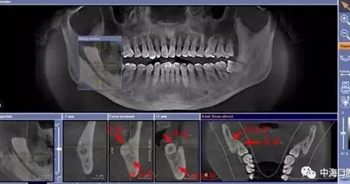

由于智齒的生長位置特殊,導(dǎo)致了拔除難易不同,如智齒出現(xiàn)橫著長或者靠近牙神經(jīng)的話,則難度會較高,一般人只需拍個口腔全景片,但相對于智齒靠近神經(jīng)管的情況,還可能需要拍CT,這都很考驗牙醫(yī)的技術(shù)。

拔牙非小事,請不要拿成本衡量牙醫(yī)的價值!

下面這兩張圖,據(jù)說拔牙費時1.5小時,收費14000元。